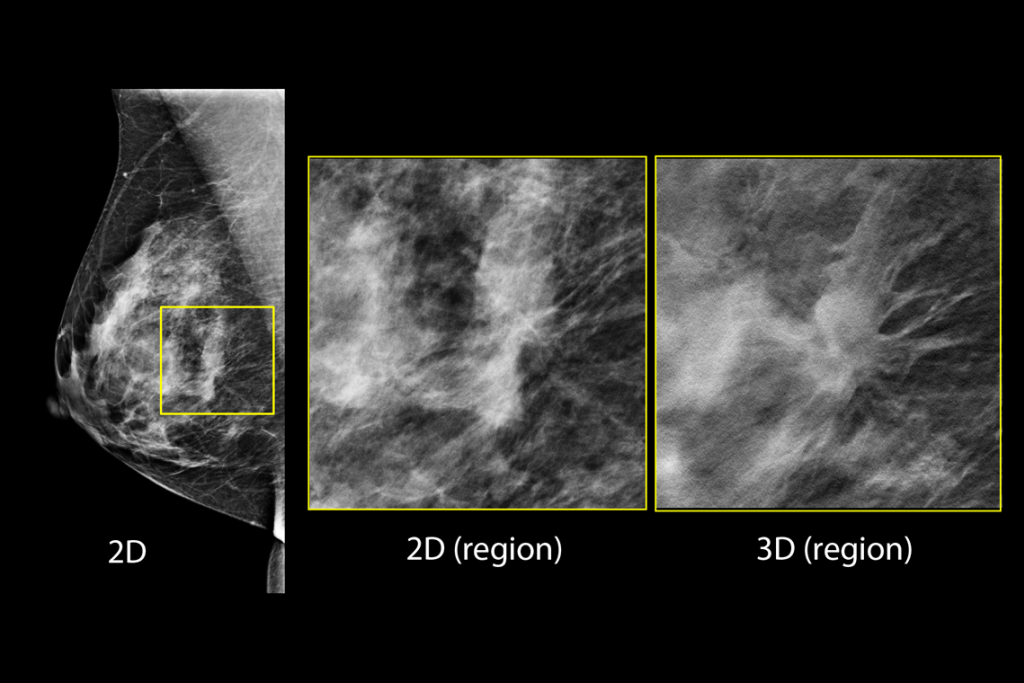

Immagini cliniche di una mammografia

Immagini cliniche di una mammografia con lesione sospetta

Immagini cliniche di una mammografia con tessuto mammario denso